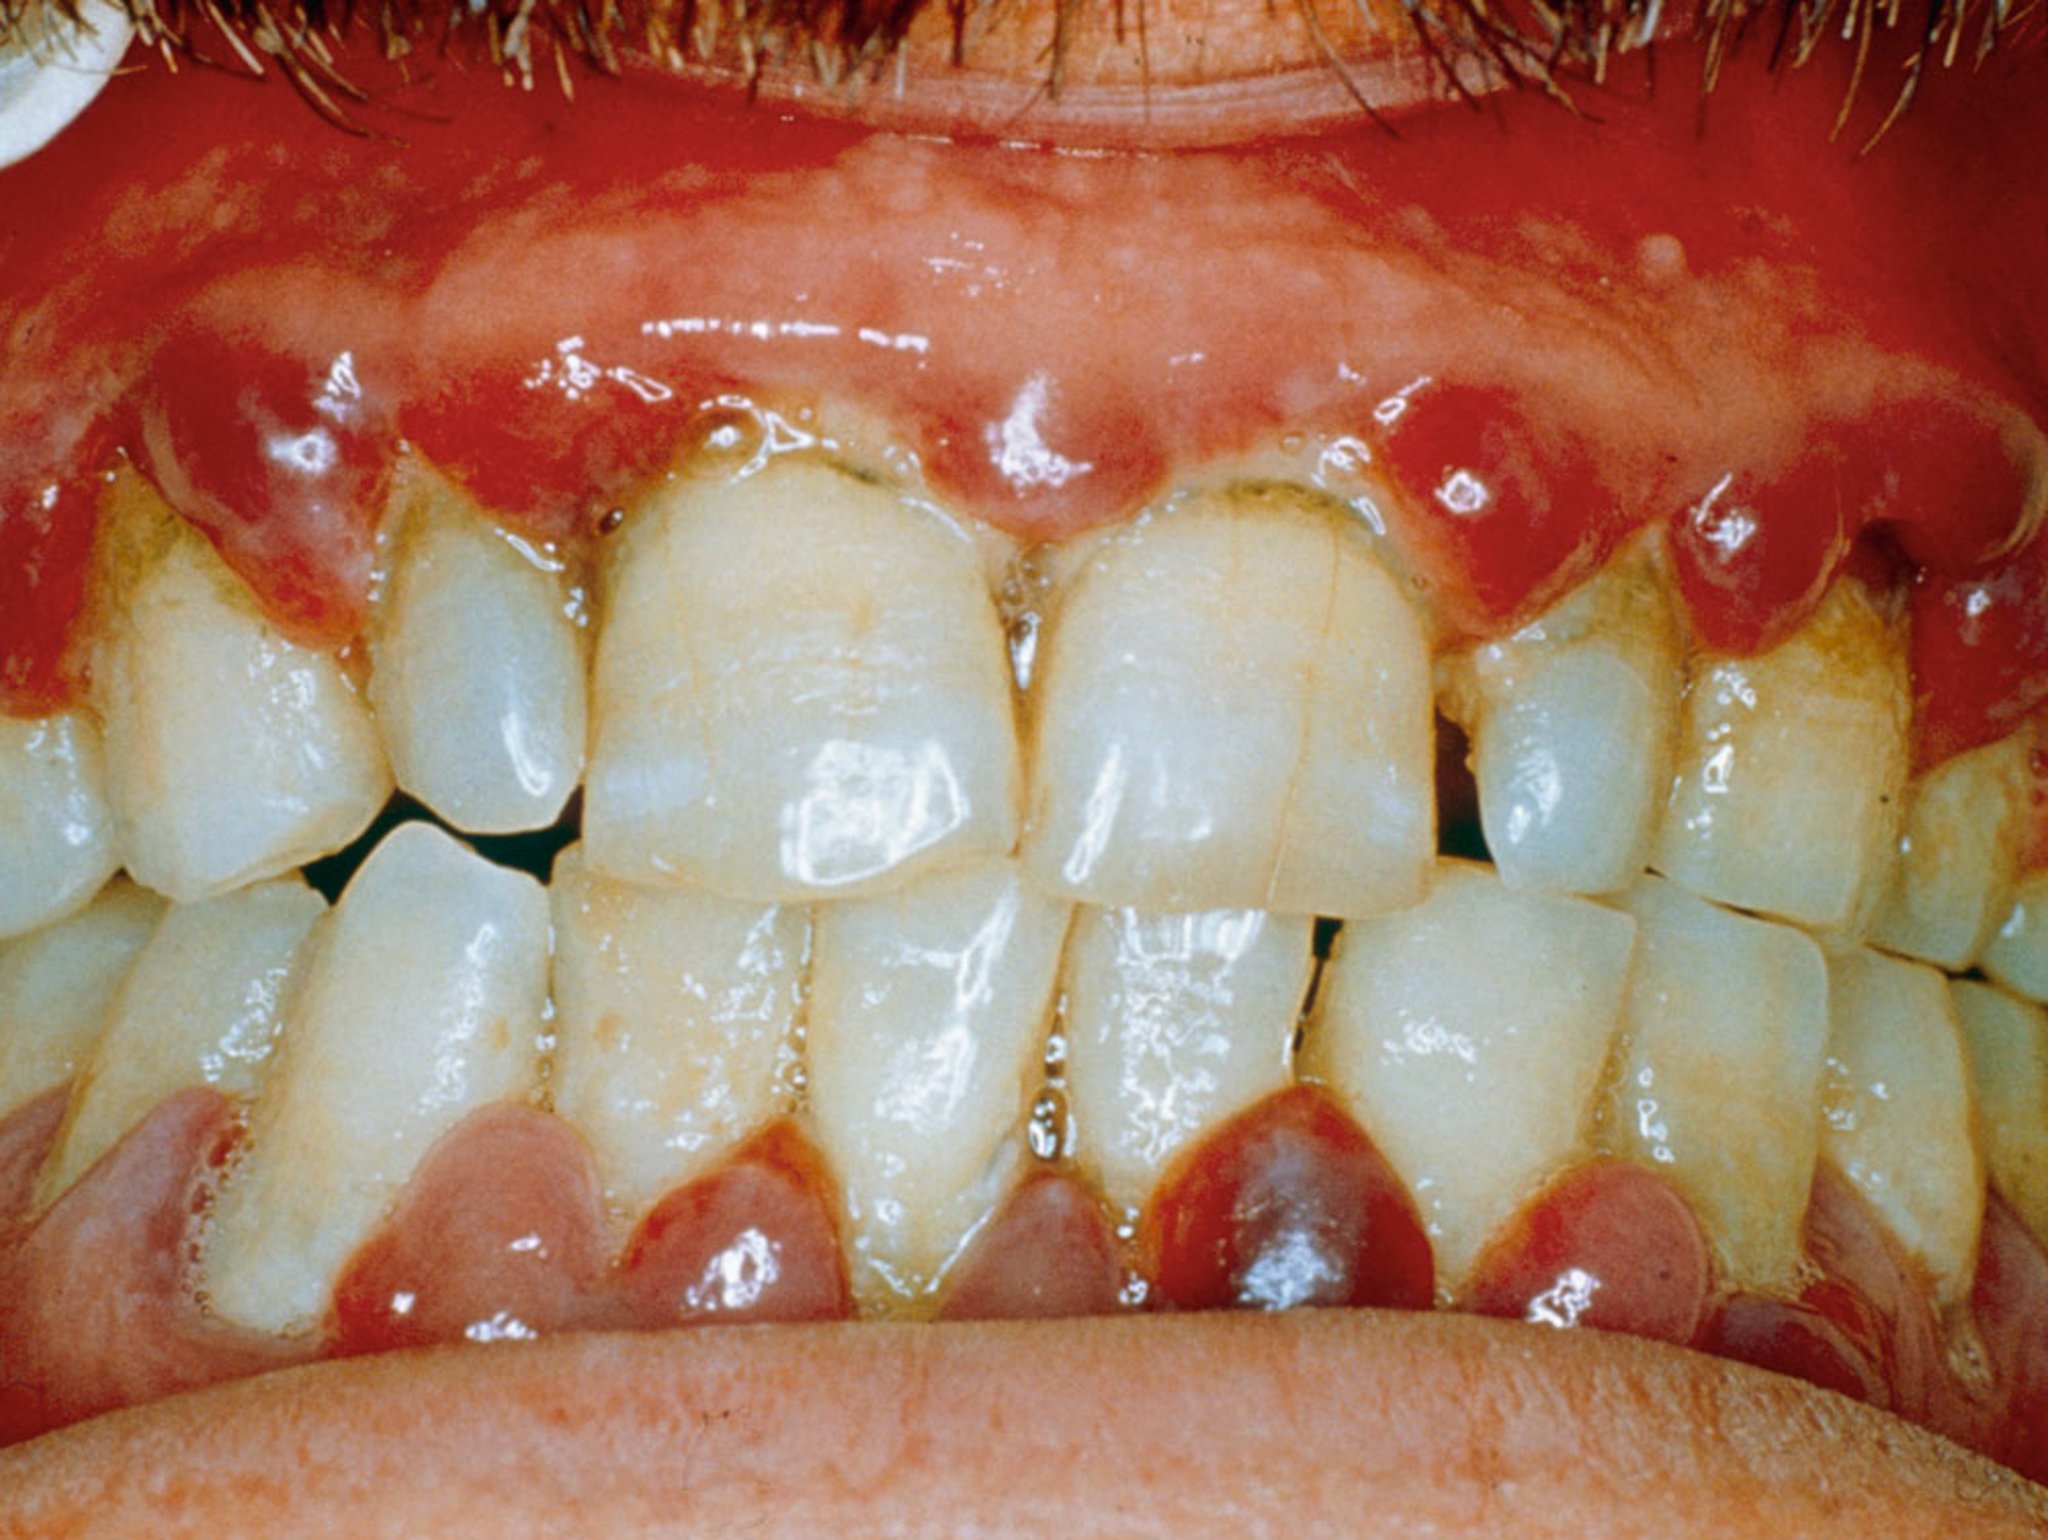

Gejala scurvy terjadi setelah defisiensi berlangsung selama beberapa bulan. Perdarahan dapat terjadi di bawah kulit (terutama di sekitar folikel rambut atau memar), di sekitar gusi, dan ke dalam sendi. Gusi menjadi bengkak, berwarna ungu, dan lunak. Gigi pada akhirnya dapat goyah. Rambut menjadi kering, rapuh, dan tergulung (seperti pembuka botol), dan kulit menjadi kering, kasar, dan bersisik. Cairan dapat terakumulasi di kaki. Anemia dapat terjadi. Infeksi dapat terjadi, dan luka tidak sembuh.